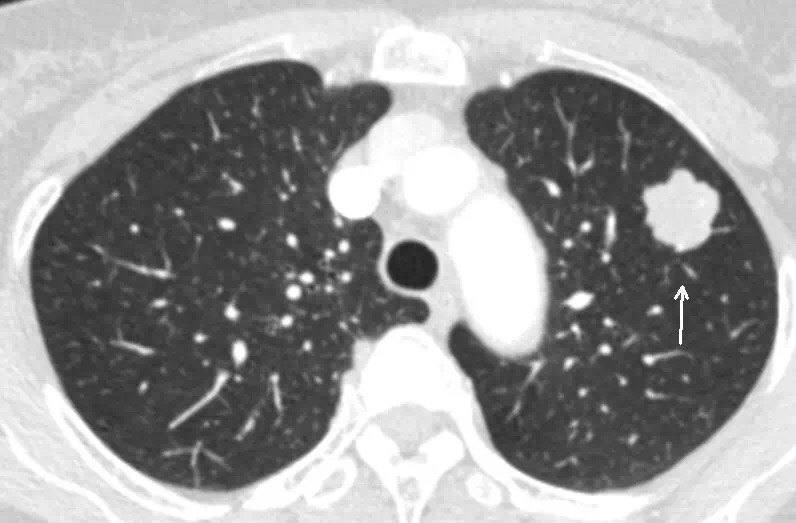

恶性肺结节图片,实性结节

实性结节

恶性肺结节ct图片

恶性肺结节